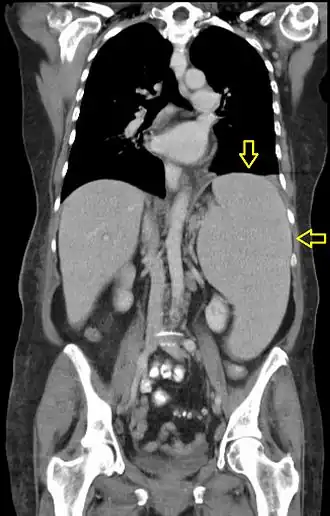

Description de l'image Splenomegalie bei CLL (labeled).jpg.

Une hépatosplénomégalie est l'association d'une augmentation de volume du foie (hépatomégalie) et de la rate (splénomégalie).

Le diagnostic se fait à la palpation de l'abdomen lors d'un examen clinique, ou en réalisant des examens complémentaires comme l'échographie abdominale, le scanner ou l'IRM.

Une hépatosplénomégalie est le signe d'une pathologie sous-jacente. On la retrouve dans de très nombreuses maladies, par exemple dans la maladie de Gaucher. Elle peut également être le reflet d'une hypertension portale souvent associée à une insuffisance cardiaque droite ou une cirrhose.